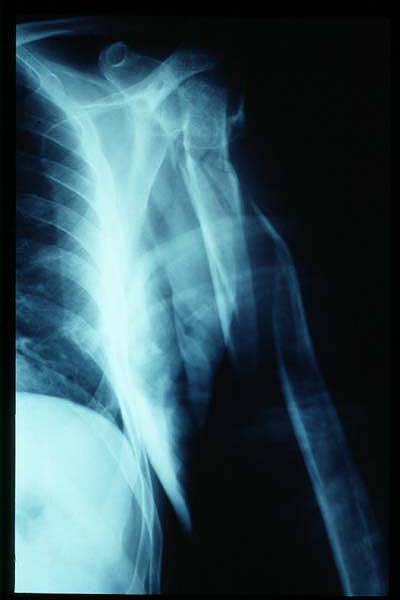

MO Fractura de omóplato y de costillas 2 a 8 derechas. Accidente de tráfico con moto en paciente centenaria. 1

MO Fractura de omóplato y de costillas 2 a 8 derechas. Accidente de tráfico con moto en paciente centenaria.2